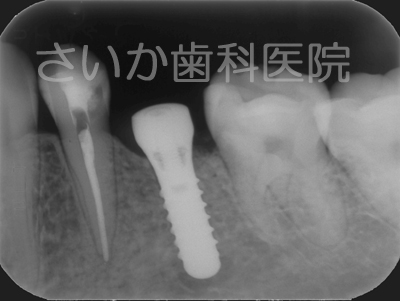

上の写真は治療前の状態です。成人の方ですが先天的に永久歯が一本少なかったので,乳歯が残っていました。その乳歯も根の吸収が進み,ぐらぐらになってきました。下のレントゲン写真を見ていただければ根がなくなっているのがわかります。

両隣に歯がありますからブリッジでも治療できるケースです。出来るだけ健全な歯はそのままにして治療するという方針で,インプラントを利用しました。下のレントゲン写真がインプラントを入れた手術後のものです。